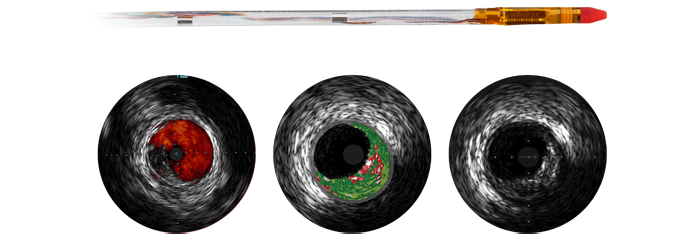

Catéter digital de ultrasonidos intravasculares

Eagle Eye Platinum

El catéter digital de ultrasonidos intravasculares Eagle Eye Platinum es la primera opción de facultativos especializados en adquisición de imágenes intravasculares (EE. UU.). *Al tratarse de un catéter para adquisición de imágenes intravasculares plug and play con prestaciones exclusivas, está diseñado para que sea fácil de usar y ofrecer una gran capacidad de administración. Algunas de sus características son una punta cónica blanda, recubrimiento hidrofílico GlyDx para una mayor lubricidad, una luz larga de intercambio rápido para que sea más fácil de presionar, tres marcadores radiopacos y compatibilidad con IntraSight y SyncVision para reposicionamiento automático con angiografía.

* Tenga en cuenta que este producto puede no estar disponible en su país. Para obtener información sobre la disponibilidad, consulte a su representante local de ventas.You are about to visit a Philips global content page

Cociente instantáneo de presión libre de ondas: iFR

El índice fisiológico sin hiperemia líder para medir la presión en procedimientos diagnósticos e intervencionistas, que puede mejorar los resultados, ahorrar tiempo y reducir las molestias para el paciente. iFR se mide con el primer cable guía de presión de núcleo sólido del mundo, OmniWire, con valores reposicionados* directamente en la angiografía. Esta orientación fisiológica avanzada ayuda a identificar con precisión qué partes de un vaso están causando isquemia, lo que facilita la elección del tratamiento.

* Disponible con IntraSight 7 y SyncVisionYou are about to visit a Philips global content page

Cable de guía de presión

OmniWire

OmniWire combina un diseño polivalente de núcleo sólido exclusivo con resultados probados de iFR y compatibilidad con reposicionamiento automático de iFR, lo que facilita el uso de la fisiología en casos complejos¹,²,³. El nuevo núcleo distal de nitinol aumenta la durabilidad y la recuperación de la forma. El núcleo sólido exclusivo mejora la torsión y la presión. Incluye bandas conductoras para una mayor fiabilidad de la señal.